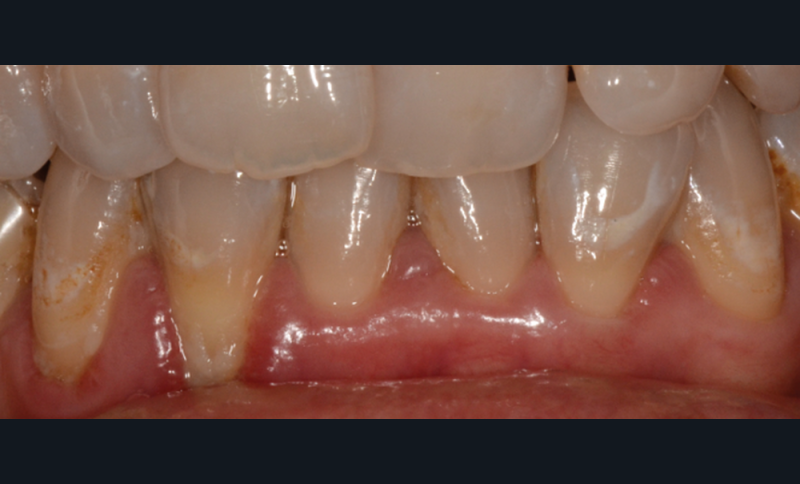

Quelle insatisfaction et quelle déception de constater, en cours ou à l’issue d’un traitement orthodontique, la fragilisation du parodonte, voire l’apparition d’une récession gingivale !

Le plan de traitement était-il le bon ? Fallait-il renforcer les tissus de soutien de la dent de manière préventive ?

C’est à ces questions que nous permettront de répondre les deux premiers conférenciers, parodontologistes : le Dr Béatrice Straub nous présentera le renfort parodontal minéralisé, technique qu’elle a développée et pratique depuis de nombreuses années, pour éviter les préjudices des mouvements orthodontiques à risque, notamment lors des décompensations préchirurgicales (fig. 1a-d) ; le Pr Anton Sculean abordera le thème des greffes, avec leurs indications, les différentes techniques à privilégier et illustrera ses propos par de nombreux cas cliniques aux résultats esthétiques impressionnants.